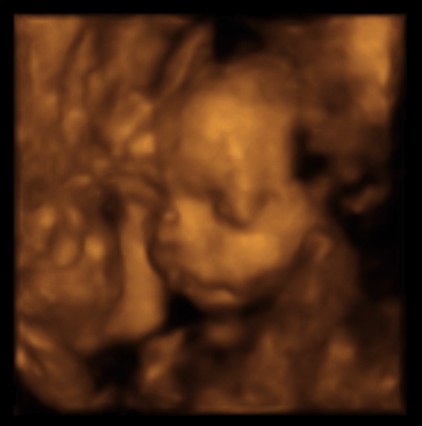

Har været til 3D scanning, hvilket var en fantastisk oplevelse...

Synes lige jeg ville dele nogle af billederne med jer....Så her har i lille Madicken

Hvor ser ud dog fin ud!!!!